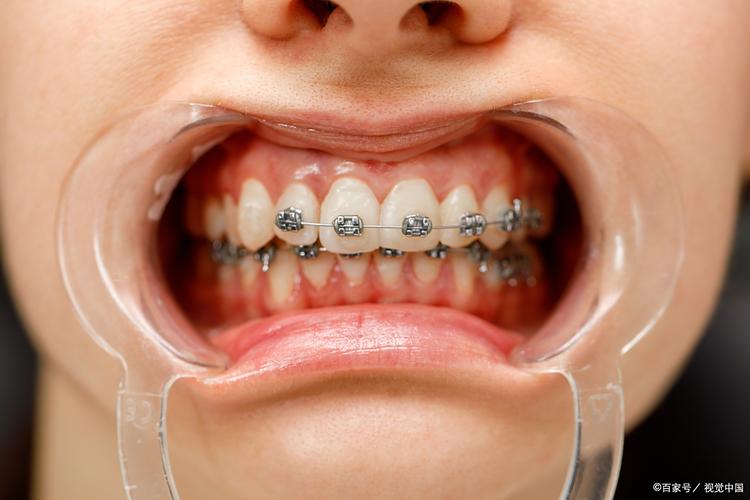

- 矫治器选择:根据患者年龄、美观需求及牙齿复杂度选择合适的矫治器:

- 传统固定矫治器:即“钢牙套”,通过托槽和弓丝施加力量,适用范围广,尤其适合牙齿倾斜严重、需要复杂移动的患者;

- 自锁托槽矫治器:摩擦力较小,牙齿移动速度更快,复诊间隔延长,患者不适感较低;